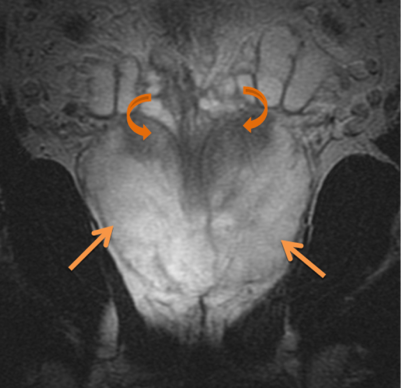

Anatomic delineation of the prostate and the apex using CT has not been without controversy. To attempt to resolve this several methods of identifying the apex were used:

Poor correlation of the prostate apex was found between these modalities. The retrograde urethrogram was tested to insure that the urethrogram itself did not displace the prostate by pre- and post-urethrogram MRI studies which demonstrated no artifactual displacement as a result of the urethrogram. Roach examined 10 patients and noted that the prostate volume was 32% larger on non-contrast CT than when determined by MRI. The regions of most non-agreement were posterior-inferior (neurvascular bundles) and posterior extent of the gland. The CT volume for prostate and seminal vesicles was 40% larger on the average than the MR with the CT variant 8 mm larger at the base of the SV and 6 mm larger at the apex. This was corrected for and persistent with interobserver variation.

There is significant variation of contours and techniques. The apex and base are regions most susceptable to variation. 3D perspectives help signficantly reduce this variation using transverse, sagital and coronal projections to determine the true extent of the prostate. More recently contouring atlases have been developed by the RTOG with grant assistance from the NCI and are available here. The following images are obtained from the RTOG contour atlases as an excerpt demonstrating areas of potential uncertainty.